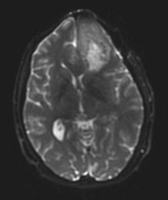

• inner part of the tumor segmented from SPGR

• outer part of the tumor segmented from post-Gad

• WM and GM segmented from N4-processed SPGR (WM segmentation of the original SPGR volume is included, note under-segmented WM in the skull base)

• all segmentations were done using FastMarching, fiducials are included for each of the segmentations

• no fine-tuning of the fiducial locations was done -- this is an example result one can get almost right away

• rule of thumb in placing fiducials: try to cover uniformly the volume you are trying to segment; this is particularly important for large structures like WM/GM